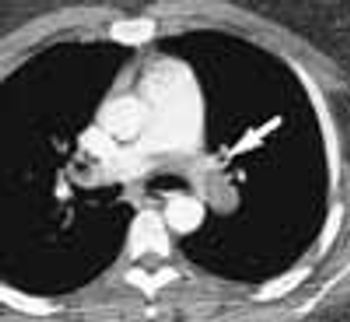

Police brought a delirious, combative 24-year-old man to the emergency department. The patient was unable to provide any history on arrival, but his scarred, blistering lips and his vital signs (blood pressure, 166/102 mm Hg; heart rate, 97 beats per minute; respiratory rate, 24 breaths per minute; and temperature, 38.2°C, or 100.9°F) led to a possible diagnosis of cocaine-induced delirium.